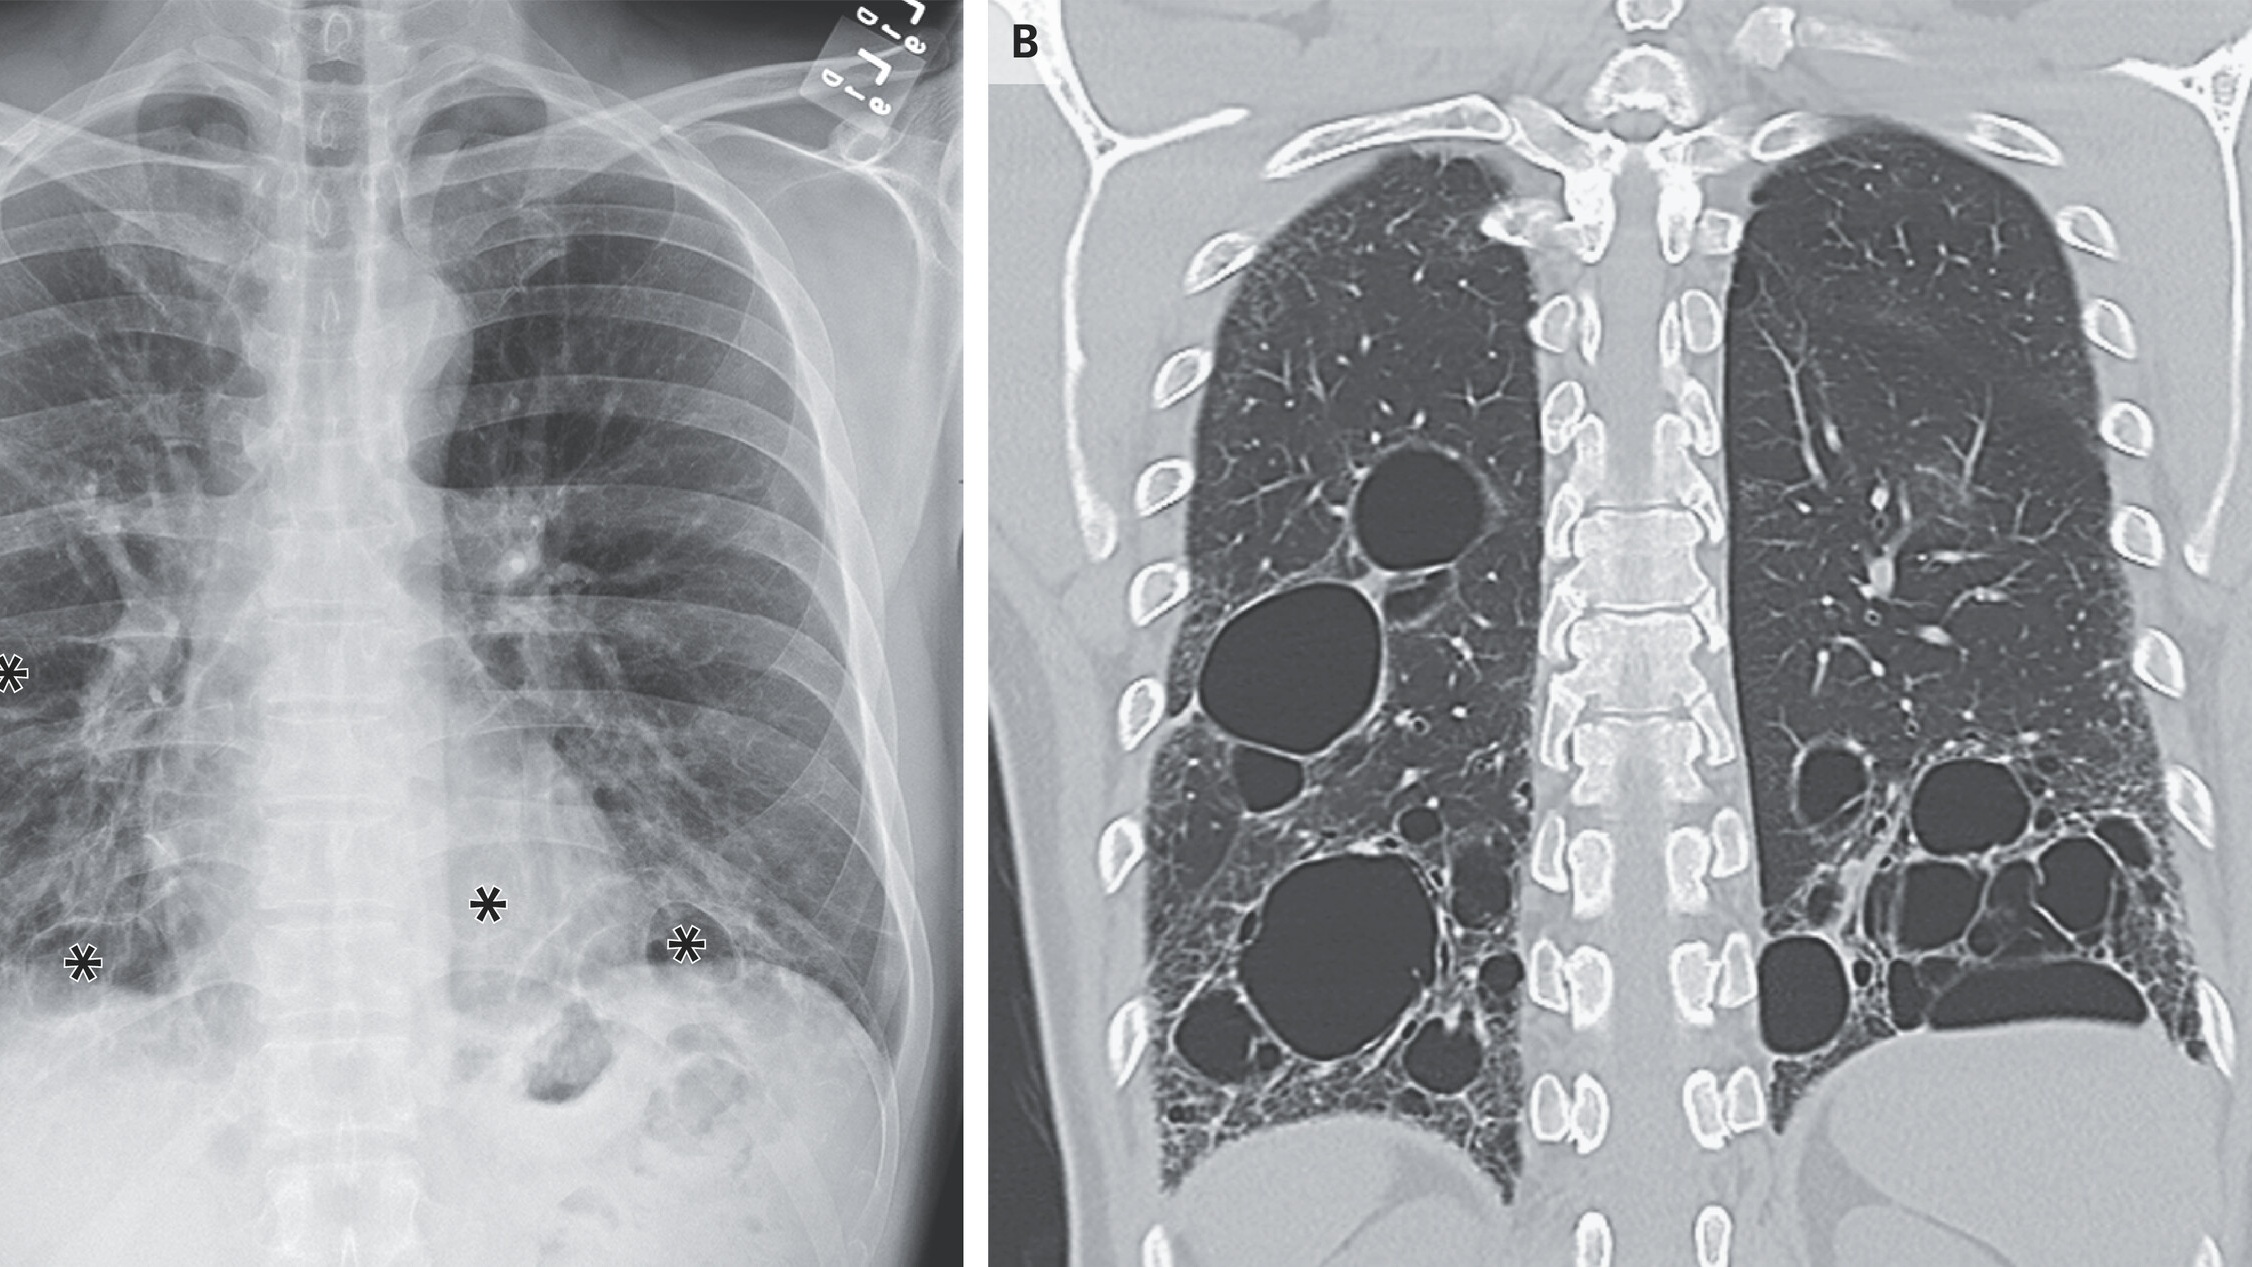

- Chẩn đoán hình ảnh: Chụp X-quang ngực hoặc chụp CT để có cái nhìn rõ hơn về phổi và giúp chẩn đoán viêm phổi kẽ.